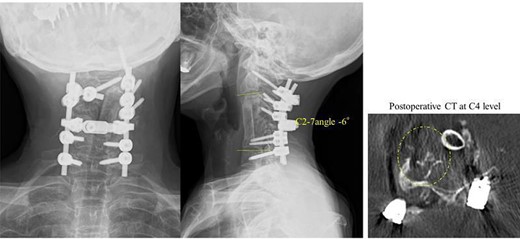

In the second stage, bilateral resection of the fused C3/4, 4/5 and 5/6 facet joints and C3–5 laminae was performed, followed by corrective fixation of C2-T1 (C2, C7 and T1 pedicle screws and C3 and C4 lateral mass screws were placed and corrected with lordotic rod). The C2–7 angle was corrected from −65° to −6°. In the third stage, an autologous fibula was grafted into the space created after resection (Fig. 4).

Radiography image after the three-stage combined surgery; cervical alignment was improved after this approach (the C2–7 angle was corrected from −65° to −6°).